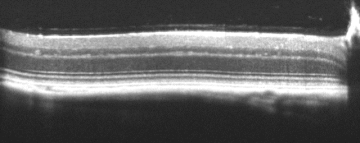

Bioptigen sdOCT Imaging System

Sample Bioptigen sdOCT Imagery:

Retina